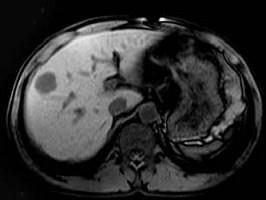

问题 男,42岁。体检B超发现肝内占位,行MRI检查见肝右叶长T1长T2异常信号。依据MRI图应诊断为 ( )

选项 A、肝脏单发转移瘤 B、未见异常 C、肝血管瘤 D、肝癌 E、肝囊肿

答案 C